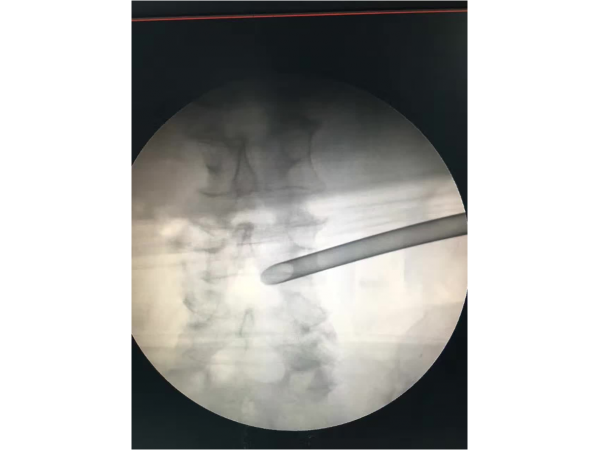

產品說明:1.手術體位:體位可以采用俯臥位和側臥位,我們習慣于采用俯臥位來完成PELD手術。2.畫線:先畫出腰椎棘突的連線,再畫出雙側髂嵴

產品說明:腰5/骶1椎間盤突出癥、側隱窩骨性狹窄。經保守治療無效,后主管醫(yī)生陳永紅副主任醫(yī)師為患者實施局部麻醉下微創(chuàng)椎間孔鏡治療,術

產品說明:這是一位中年男性,有著5年頸段食道腫瘤和2年“胃造瘺術”病史的多病患者。3月前出現腰部、左臀部及小腿酸痛不適,癥狀逐漸加重